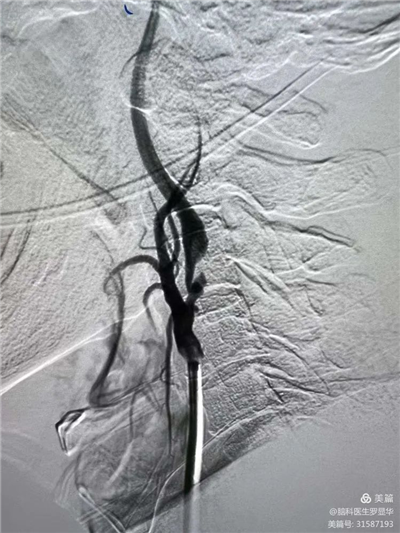

手術(shù)過程:指引導(dǎo)管到位

手術(shù)過程:球囊擴張后,protege支架到位

術(shù)后造影示狹窄解除